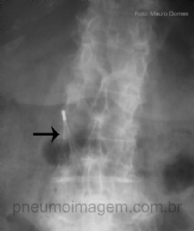

CASO CLÍNICO #22

Qual o nome desse sinal e o que ele significa? Deixe seus comentários abaixo. *** What is the name of the sign and what it means? Leave your comment below.